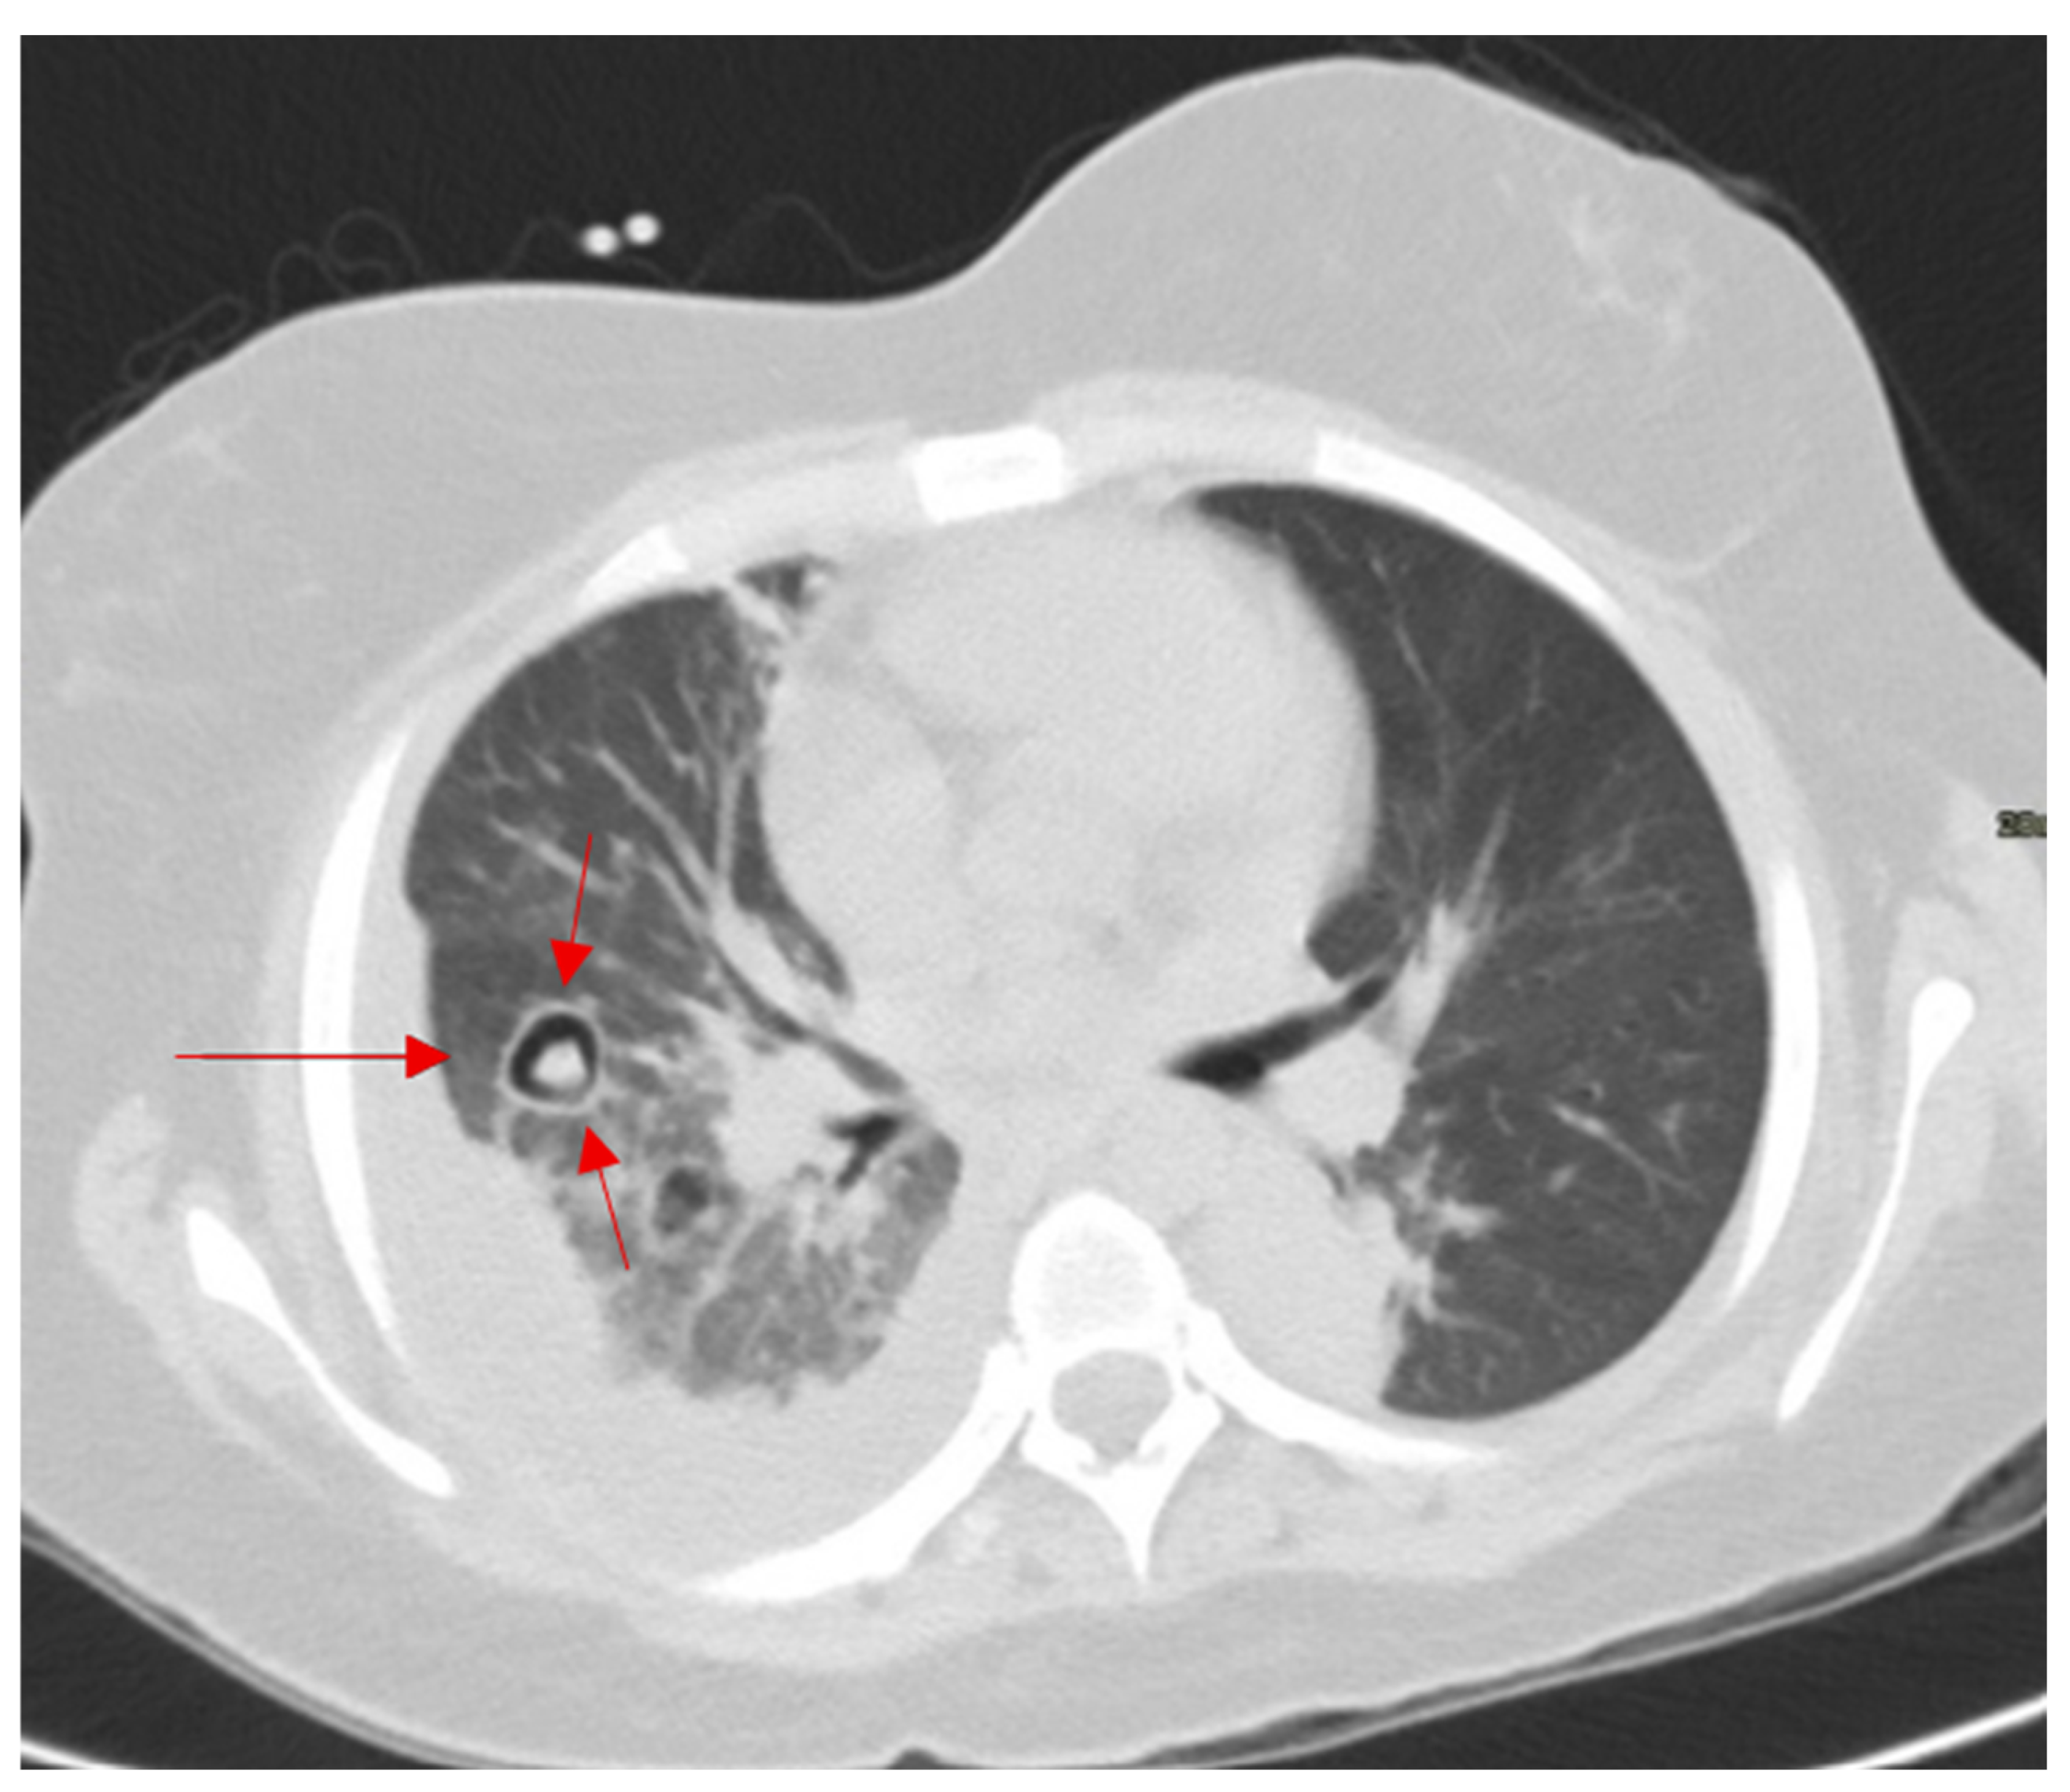

2.15. Halo Sign

| Air Crescent Sign | CT chest | Invasive pulmonary aspergillosis (IPA), cavitary lung disease | Seen in ~50% of IPA cases; not exclusive | Often coincides with neutrophil recovery in IPA, improving prognosis; must be interpreted with clinical and microbiological data. |